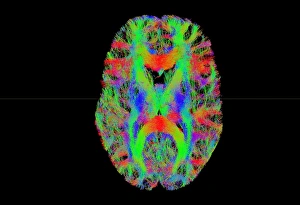

The central nervous system, the intricate network that governs our every thought and movement, is a marvel of complexity. From the delicate cerebellum tissue to the detailed light micrograph capturing its essence, we are reminded of its importance in maintaining balance and coordination. Anatomy comes alive as we explore the human brain from an inferior view. The intricacy of brain fibers is revealed through DTI MRI scans like C017/7099 and C017/7035, showcasing their vital role in transmitting information throughout this extraordinary organ. Artistic renderings bring us closer to understanding the medulla oblongata's significance within the brain. Its portrayal in various artworks allows us to appreciate how it controls essential functions such as breathing and heart rate. As we delve deeper into studying the central nervous system, models of the human brain provide invaluable insights into its structure and organization. Lateral views reveal countless regions responsible for cognition, emotion regulation, sensory perception, and motor control. Microscope slides offer glimpses into nerve cells' intricate architecture—a testament to their ability to transmit electrical signals at lightning speed. Meanwhile, glial stem cell cultures captured under a light microscope remind us of their crucial role in supporting neuronal function. Finally, artistic representations unveil the limbic system's enigmatic nature—an interconnected web responsible for emotions and memory formation. These captivating artworks allow us to visualize this complex network within our brains. Exploring these hints provides a glimpse into the awe-inspiring world of our central nervous system—the very foundation upon which our thoughts, actions, memories reside—reminding us just how remarkable our brains truly are.